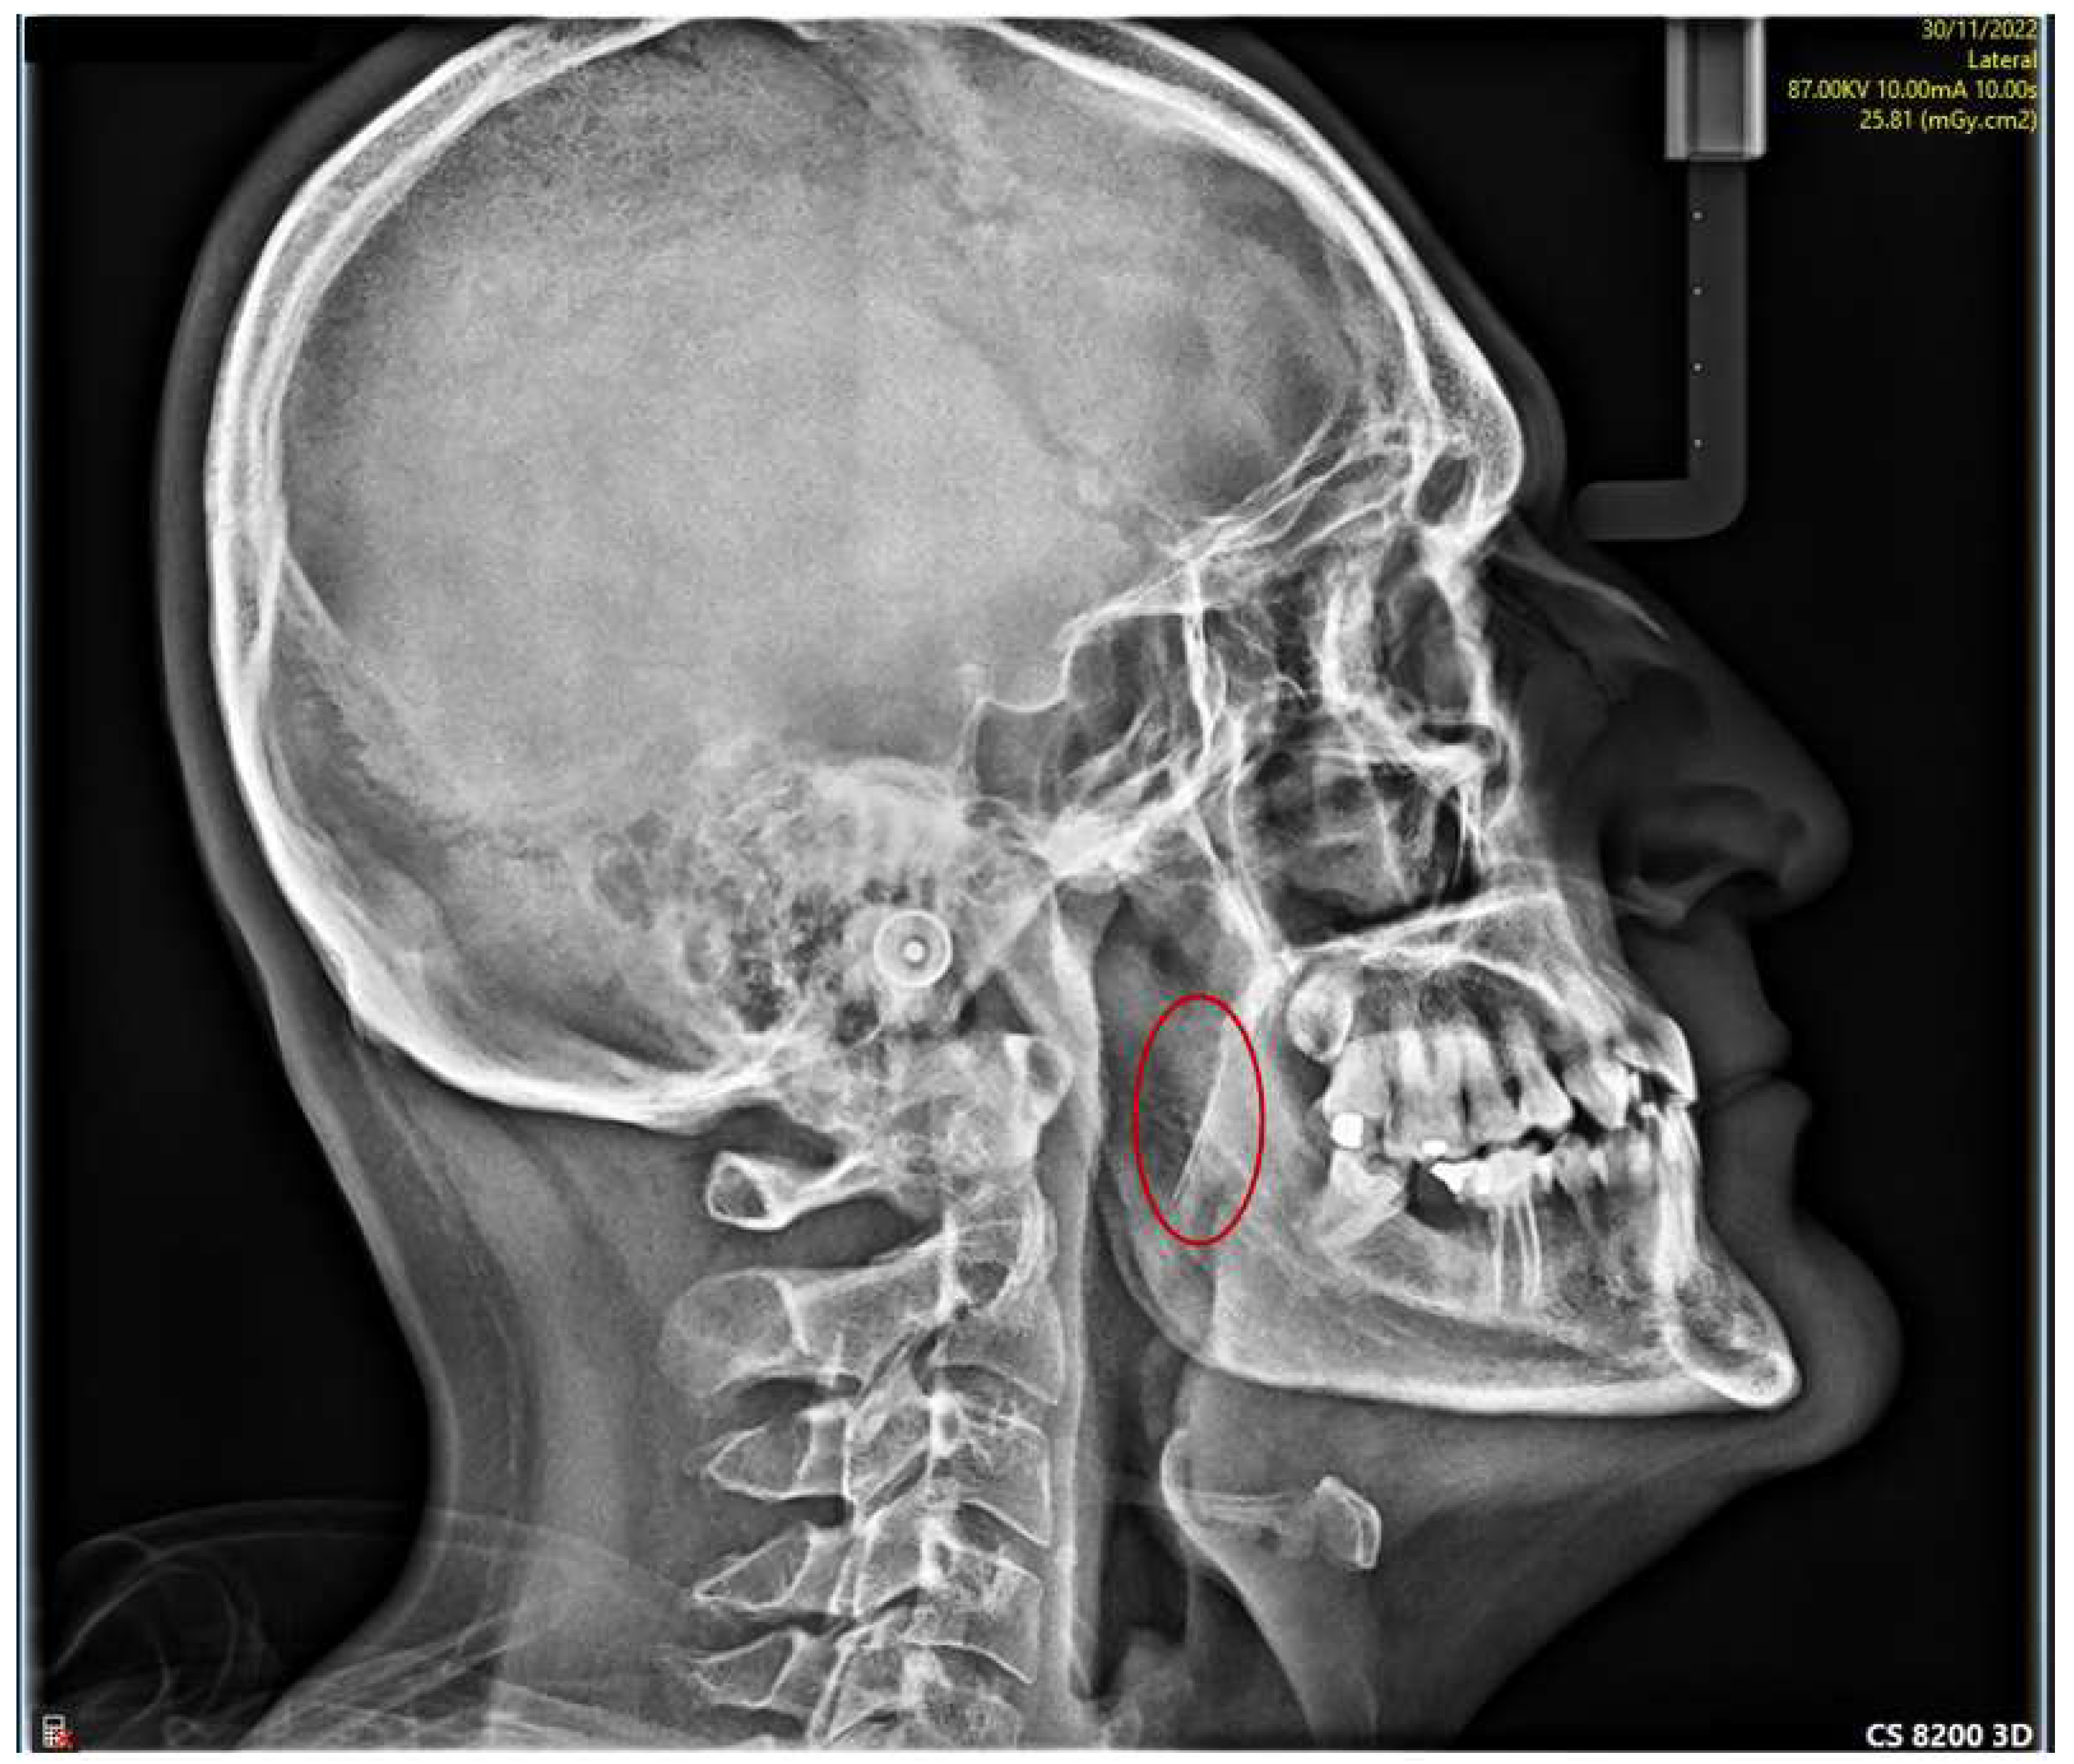

5. Case Report